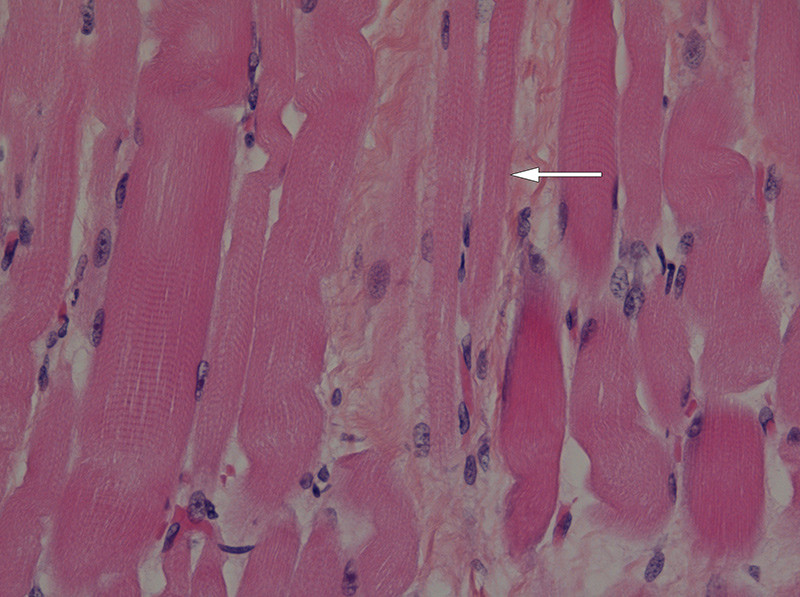

Figure 3  Biopsy of diaphragm showing atrophic muscle fibres (arrow). Photo Christina Vogt